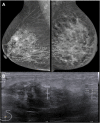

Breast metastases from extramammary cancers are rare and usually related to poor prognosis. The extramammary tumours most frequently exhibiting breast metastases are melanoma, lymphomas, ovarian cancer, lung and neuroendocrine tumours, and sarcomas. Owing to the lack of reliable and specific clinical or radiological signs for the diagnosis of breast metastases, a combination of techniques is needed to differentiate these lesions from primary breast carcinoma or even benign breast lesions. Multiple imaging methods may be used to evaluate these patients, including mammography, ultrasound, MRI, CT and positron emission tomography CT. Clinical and imaging manifestations are varied, depend on the form of dissemination of the disease and may mimic primary benign and malignant breast lesions. Haematologically disseminated metastases often develop as a circumscribed mass, whereas lymphatic dissemination often presents as diffuse breast oedema and skin thickening. Unlike primary carcinomas, breast metastases generally do not have spiculated margins, skin or nipple retraction. Microlobulated or indistinct margins may be present in some cases. Although calcifications are not frequently present in metastatic lesions, they occur more commonly in patients with ovarian cancer. Although rare, secondary malignant neoplasms should be considered in the differential diagnosis of breast lesions, in the appropriate clinical setting. Knowledge of the most common imaging features can help to provide the correct diagnosis and adequate therapeutic planning.